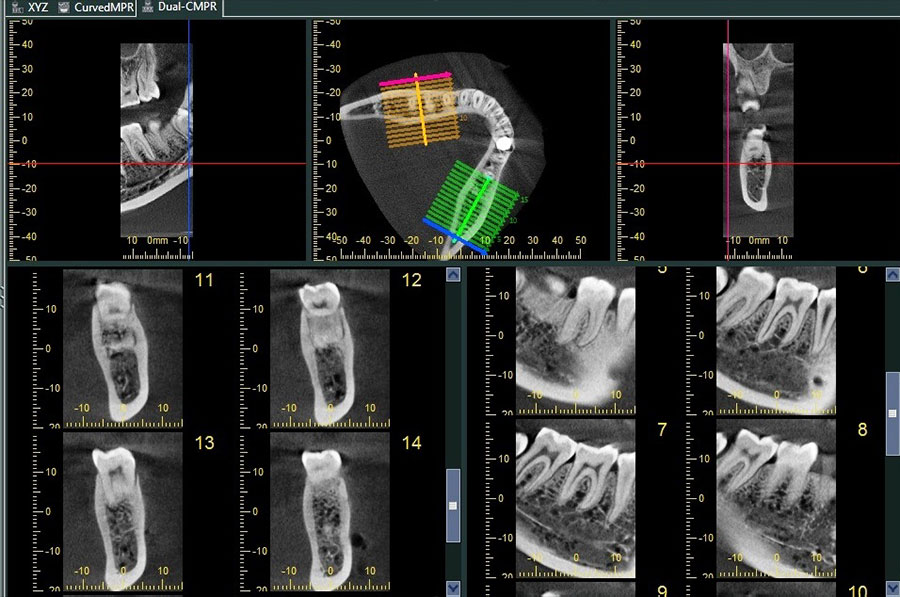

Dental tomografi X ışını kullanmak suretiyle ilgi alanı dışındaki görüntülerin odak dışında bırakılarak istenilen bölgedeki objelerin daha net bir şekilde görülmesini sağlayan, ince kesitlerden oluşan ve hacim içeren görüntü elde etmeye yardımcı olan bir yöntemdir. Klasik diş röntgeni ile arasındaki ana fark, bir volumetrik tomografinin bize 3D görüntü verebilmesidir. Bu da uzunluk, genişlik ve derinlik de dahil üç boyutlu görüntüleme ve tüm dişlerin, çene kemiğinin ve hatta hava yolunun etrafını görebilmemiz anlamına gelir!

Dental konik ışın bilgisayarlı tomografi (CBCT) teknolojisi, diş hekimlerinin hastalarını daha etkili bir şekilde tedavi etmelerine olanak tanıyarak diş radyografik görüntülemenin sonuçlarını kökten değiştirmiştir. Bu teknoloji, diş hekimlerinin saf tanıyı daha doğru yapmalarını sağladığı gibi, hekimlerin tanı ile yetinmeyip daha ileri bir aşamaya geçerek tedavi simülasyonlarını planlamasına izin vermiştir.

Üç boyutlu tomografiler ile maksillofasiyal anatominin çoğunu görüntülemek mümkündür. Daha geniş görüş alanlı CBCT genellikle çene cerrahisi ve ortognatik cerrahi uzmanlık pratiğinde uygun olanıdır, daha küçük görüş alanlı CBCT’ ler ise implant planlamadan, çatlak tespitine, endodontiden, lezyon görüntülemeye kadar her türlü detaylı tanı gerektiren tedavide kullanılabilir.